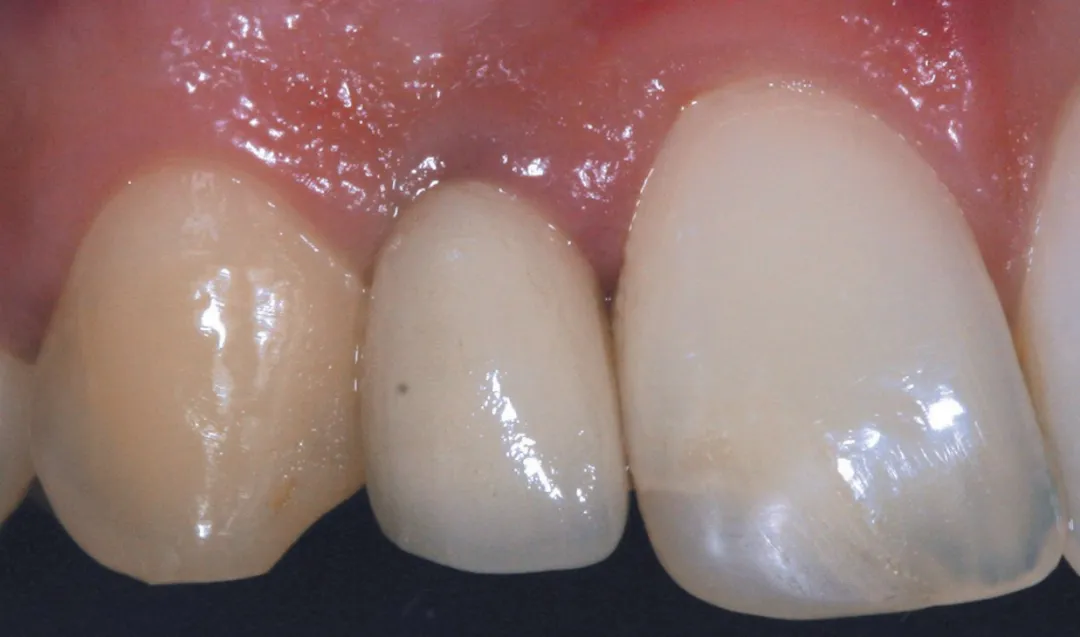

图 4 : 种植体植入位点。

图 48 :术后 1 年口内情况。